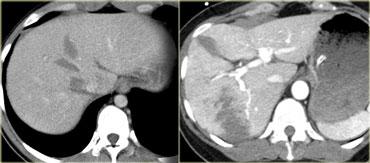

Bên trái là hai ví dụ khác về đường rách gan.

Các đường rách có thể có hình sao, như ví dụ bên trái, hoặc hình phân nhánh như ví dụ bên phải.